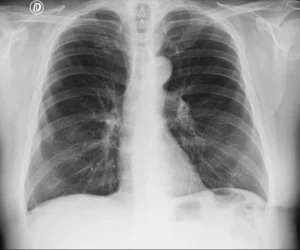

Aparente aumento de la silueta cardíaca en la Rx en decúbito supino

Paciente adulta hospitalizado que realiza una radiografía de tórax en decúbito supino, como parte de la evaluación clínica inicial.

Radiografía de tórax en proyección anteroposterior (AP), obtenida en la cama del paciente, en decúbito supino, con inspiración subóptima. La segunda radiografia se obtuvo en proyeccion PA con el paciente de pie, observandose la silueta cardiaca de tamaño normal.

C – Corazón y mediastino

La silueta cardíaca se observa aumentada de tamaño, con contornos conservados. La relación cardiotorácica se encuentra aumentada.

Este hallazgo debe interpretarse en el contexto de una proyección anteroposterior, que produce una magnificación aparente del corazón debido a la mayor distancia entre la estructura y el detector.

Este caso ilustra el aparente aumento del tamaño de la silueta cardíaca observada en la radiografía de tórax obtenida en decúbito supino, en una proyección qué necesariamente es anteroposterior (AP).

En la proyección AP, especialmente en pacientes encamados, la silueta cardíaca se encuentra más alejada del detector, lo que produce una magnificación aparente del tamaño del corazón. Este efecto geométrico puede simular cardiomegalia en ausencia de un aumento real del tamaño cardíaco.

Por este motivo, la valoración del tamaño de la silueta cardíaca debe realizarse preferentemente en una radiografía PA obtenida en bipedestación. En la proyección AP, el hallazgo de un corazón aparentemente aumentado debe interpretarse con cautela y siempre en correlación con la técnica del estudio y la clínica del paciente.